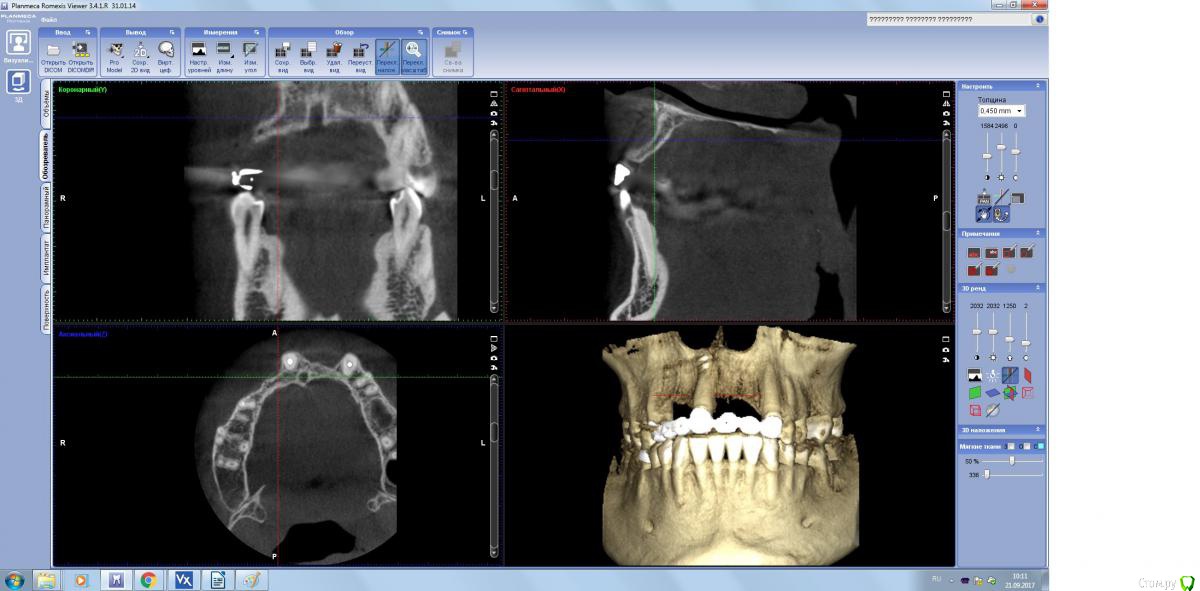

1ый сегмент не очень удобен для фиксации пластины. Проще будет сосидж и перекрыть Вип ст. Зубы (11,23)лучше оставить. А какой дизайн разреза будет в первый раз?

Не верю я особо в сосидж то во фронте, в цитопласт верю, но его не успеют привезти.. а дизайн разреза стандартная трапеция.